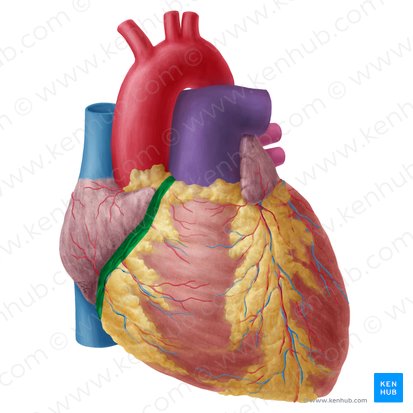

Anterior Interventricular Artery

Circumflex Branch

Coronary Artery

Coronary Sinus

Anterior Interventricular Sulcus

Coronary Sulcus

Small Cardiac Vein

Anterior Cardiac Vein

Marginal Branch

Circumflex Artery

Great Cardiac Vein